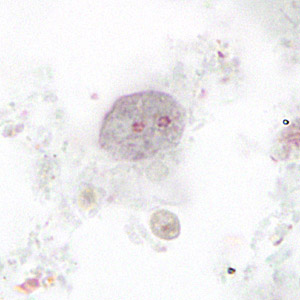

E. histolytica trophozoite

single nucleus with centrally placed karyosome. Cytoplasm contains ingested RBC’s.